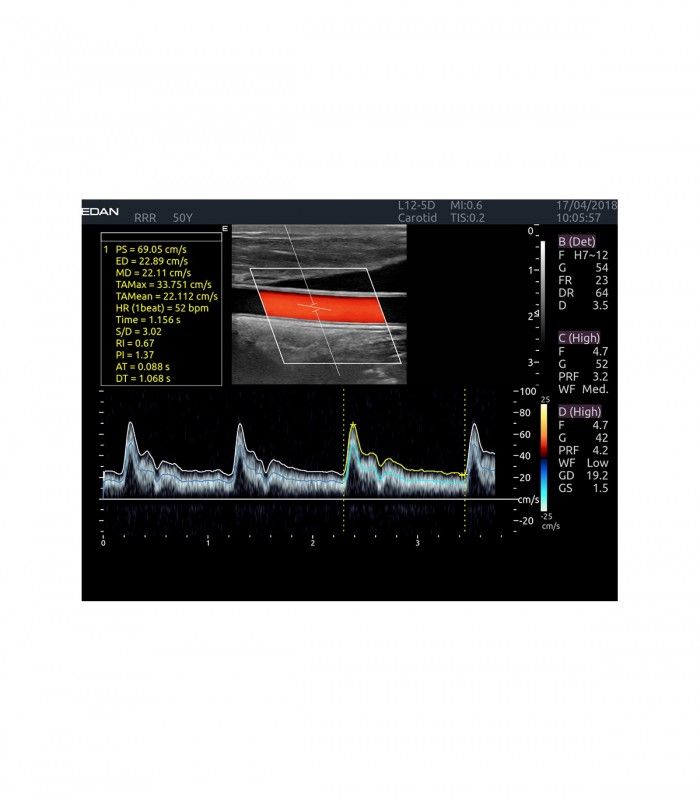

L’AX4 affiche une image claire et précise dans les différents modes grâce à de multiple technologies de traitement de l’image.

En mode couleur, les préréglages et le TAI automatique temps réel facilitent l’ajustement des flux.

En mode doppler, l’Auto-Trace affiche automatiquement les mesures à l’écran, sans les réaliser manuellement.

- Imagerie entièrement automatisée (modes B, couleur, doppler, M)

- Dopplers pulsé PW, continu CW, énergie (ou puissance) PDI et DPDI